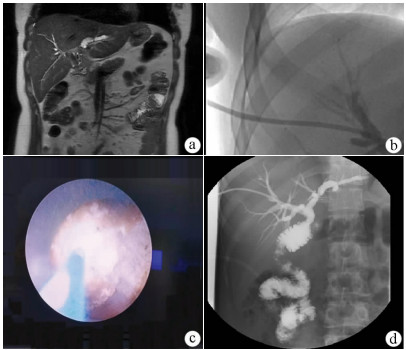

Effectiveness and safety of two-step percutaneous transhepatic choledochoscopic lithotomy in treatment of complex hepatolithiasis

Changhu DUAN, Xiaochen LIU, Jianfeng DUAN, Jianlong DING, Xirong ZHAO, Fan YANG, Lin WU, Lifei ZHAO, Sheng TAI

2021, 37(11): 2636-2641. DOI: 10.3969/j.issn.1001-5256.2021.11.029

Abstract(1120) HTML (790) PDF (1978KB)(89)

Abstract:

Objective  To investigate the clinical effect of two-step percutaneous transhepatic choledochoscopic lithotomy (PTCSL) in the treatment of complex hepatolithiasis.  Methods  A retrospective analysis was performed for the clinical data of 118 patients with complex hepatolithiasis who were admitted to 3201 Hospital of Xi'an Jiaotong University Health Science Center from January 2018 to June 2020, and according to the surgical procedure, they were divided into PTCSL group with 60 patients and surgery group with 58 patients. All patients were followed up for half a year to 3 years via telephone and outpatient service. The two groups were compared in terms of general information, perioperative indicators (including time of operation, intraoperative blood loss, incision length, time to first flatus and time to first defecation after surgery, time to extraction of abdominal drainage tube, and length of hospital stay), changes in liver function and inflammatory indicators, postoperative complications (bile leakage, acute cholangitis, wound infection, and venous thrombosis of lower extremities), stone clearance rate and recurrence rate, and quality of life. The two-independent-samples t-test was used for comparison of continuous data between two groups; the paired t-test was used for comparison between different periods of time within group; the chi-square test was used for comparison of categorical data between two groups.  Results  Compared with the surgery group, the PTCSL group had significantly shorter time of operation, time to first flatus and time to first defecation after surgery, and time to extraction of abdominal drainage tube, a significantly lower intraoperative blood loss, and a significantly shorter incision length (all P < 0.05). On day 1 after surgery, both groups had significant reductions in alanine aminotransferase (ALT) and aspartate aminotransferase (AST) (P < 0.05) and a significant increase in white blood cell count (WBC) (P < 0.05), and the PTCSL group had significantly lower levels of ALT, AST, and WBC than the surgery group (all P < 0.05). Compared with the surgery group, the PTCSL group had significantly lower incidence rates of postoperative bile leakage (5.0% vs 17.2%, P < 0.05), acute cholangitis (3.3% vs 13.8%, P < 0.05), wound infection (1.7% vs 10.3%, P < 0.05), and venous thrombosis of lower extremities (1.7% vs 12.1%, P < 0.05). Compared with the surgery group, the PTCSL group had a significantly higher stone clearance rate (58.3% vs 37.9%, P < 0.05) and a significantly lower long-term stone recurrence rate (10.0% vs 20.7%, P < 0.05). The PTCSL group had significantly higher quality of life scores than the surgery group (all P < 0.05).  Conclusion  For the treatment of complex hepatolithiasis, two-step PTCSL can effectively remove stones, with the advantages of fast postoperative recovery, low recurrence rate and incidence rate of complications, and high quality of life, and therefore, it is an effective alternative surgical procedure.